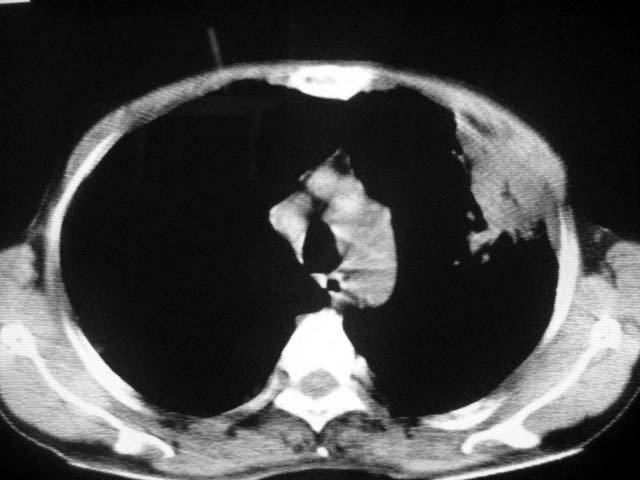

以下是引用zjzjr在2007-9-4 17:00:00的发言:[br]双上肺继发型结核伴左上肺空洞形成.慢性支气管炎伴肺气肿.

以下是引用liuzheng_9326在2007-9-4 16:23:00的发言:[br]痰检未见结核菌, 治疗后症状好转。图像符合陈旧性结核伴感染。